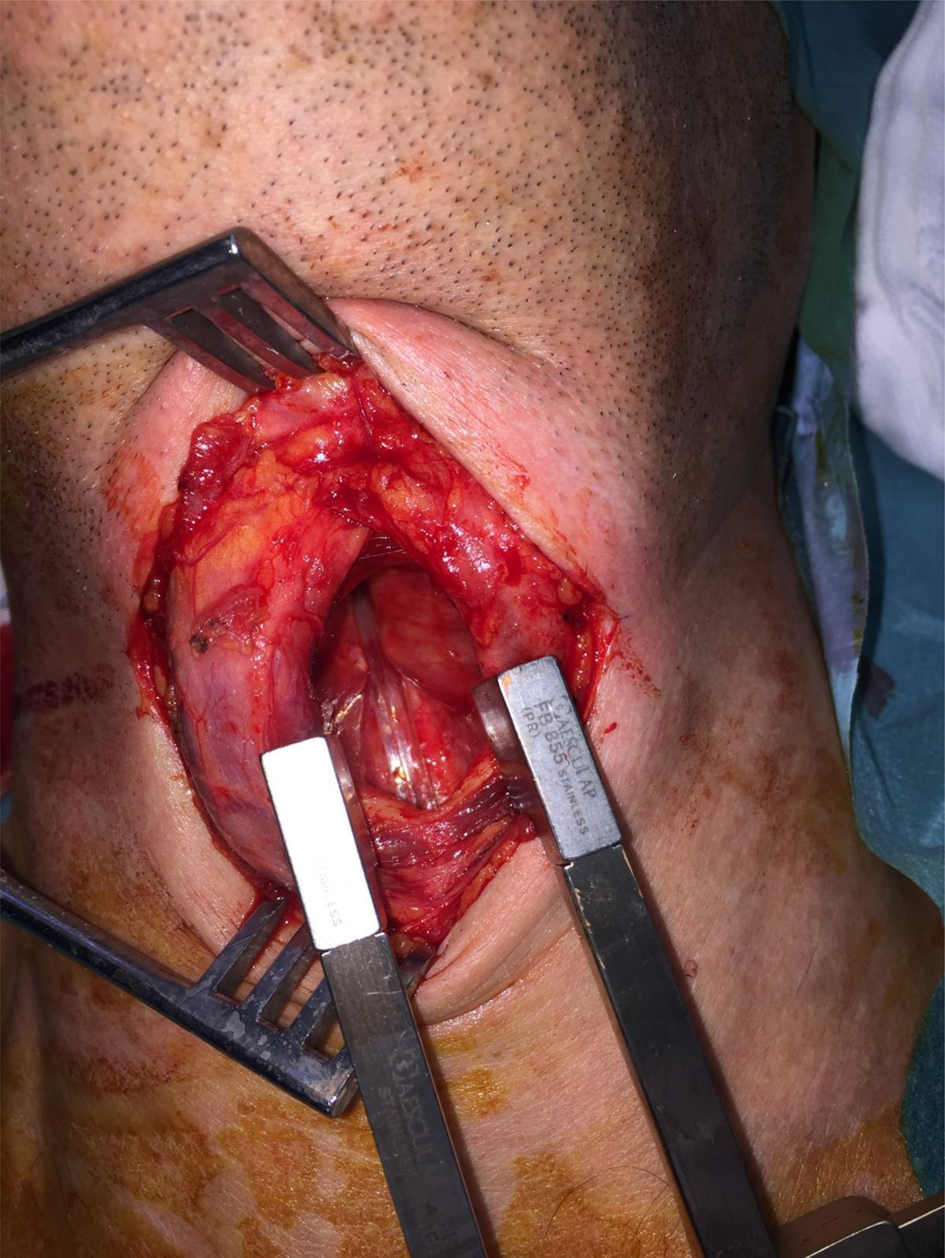

An anterior laryngofissure approach was used to obtain access to the endolarynx and the tumour. A clear view of the submucosal mass and the Tritube in the airway lumen was achieved (Figure 4). The tube did not obstruct the view of, or access to, the tumour. The tumour was resected, including the left arytenoid cartilage. Histology showed a grade I chondrosarcoma.

Fig. 4. Opening of the laryngofissure with inspection of the endolarynx. The Tritube is seen in situ. The tumour is seen on the left side. The left vocal fold was stretched over the tumour and the vestibular folds were pushed up cranially.

The main advantages of the Tritube are related to its small total diameter of 4.4 mm, combined with a pressure measurement that protects against barotrauma and a cuff that protects the airway from aspiration.Reference Schmidt, Günther, Weber, Wirth, Brandes and Barnes2,Reference Schmidt, Günther, Weber, Kehm, Pfeiffer and Becker3 Surgeons may operate freely under an acceptable view (Figure 4), and tracheostomy or intermittent apnoea may be avoided. After surgery, the patient will be able to breathe and speak normally, and use of the Tritube may result in less soreness and pain in the throat compared to a thicker tube.Reference Kristensen, de Wolf and Rasmussen4 Narrow airways may also be more easily accessed. Other advantages include avoiding direct damage during the procedure.